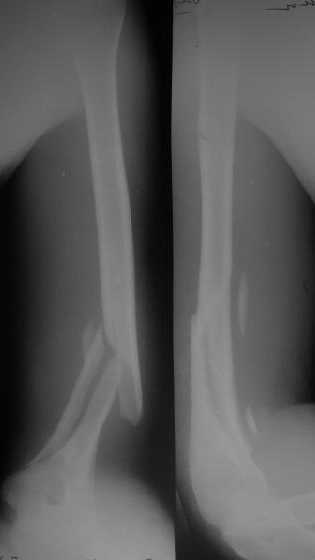

Снимки до, через 1 и 2 мес. после синтеза.